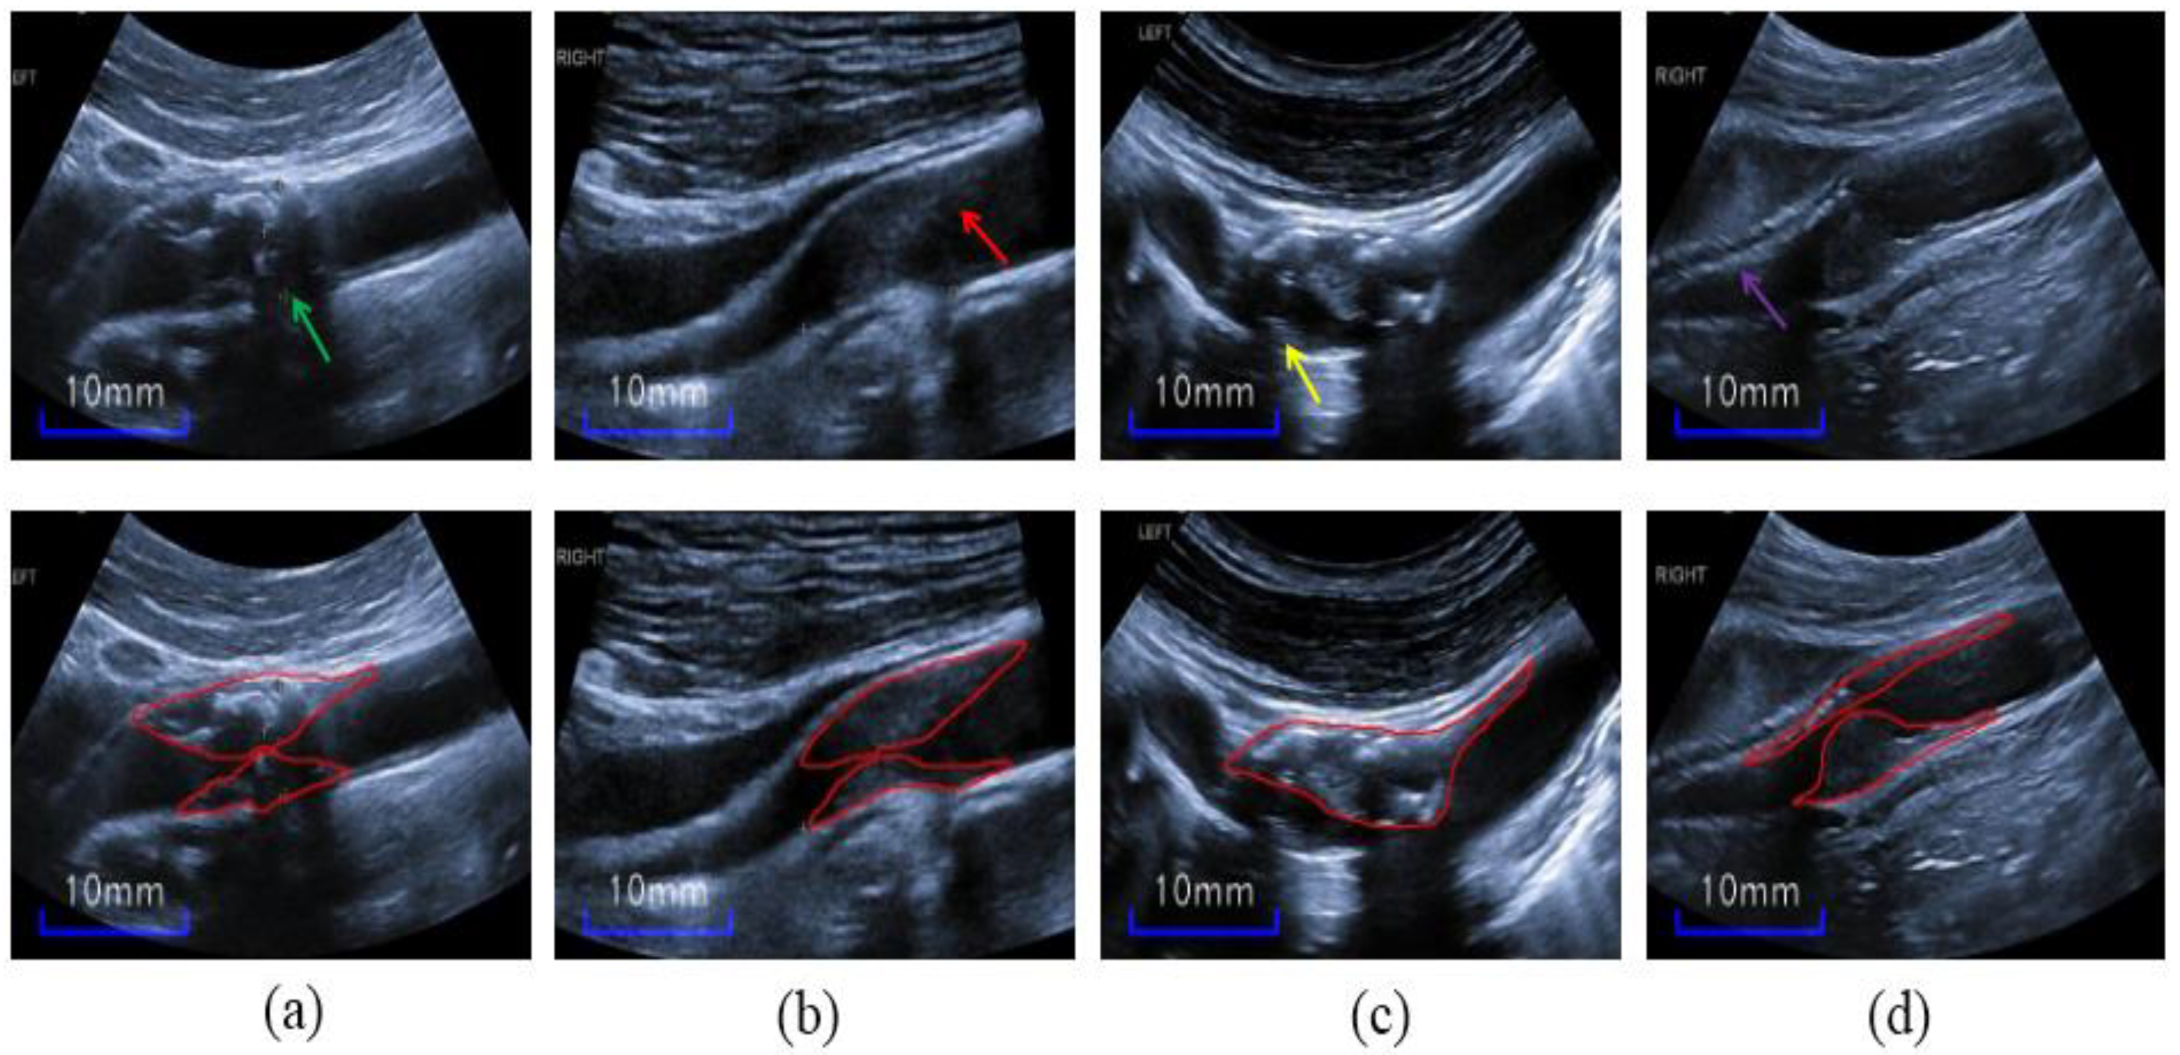

3.1. Image Augmentation

3.1.2. Cropped-Blood-Vessel Image Augmentation (CBVIA)